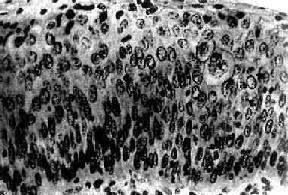

三、子宫颈原位癌子宫颈原位癌(carcinoma in situ)癌细胞局限于上皮全层内、尚未穿破上皮基底膜侵入下方固有膜。子宫颈原位癌的异型细胞比不典型增生者更具显着的多形性。镜下,上皮层完全为癌细胞所取代,细胞大小、形状不一,呈圆形、卵圆形、梭形,偶见巨核、多核,排列紊乱,层次不清,极向消失。核大浓染、大小及形状不一、染色质增粗,核分裂像常见,并有病理性核分裂像。胞浆相对减少,核浆比值增大(图13-3)。原位癌癌细胞可由表面沿基底膜伸入腺体内,致整个腺管或其一部分为癌细胞所取代,但腺管轮廓尚存,腺体基底膜完整,癌细胞未浸润到固有膜。这种变化称原位癌累及腺体。原位癌累及腺体并不一定发展为浸润癌。部分子宫颈原位癌可长期不发生浸润,个别病例甚至可自行消退。但由于原位癌特别是原位癌累及腺体具有发展为浸润癌的倾向,故一旦发现,应及时给予适当治疗。

图13-3 子宫颈原位癌 癌变限于上皮层内,细胞核肥大、深染,大小不一,形态不规则,核仁明显,核分裂像易见,且见巨细胞(右侧上方),这种细胞间变累及上皮全层,但基底膜完整,癌细胞未浸润到基底膜下间质 由于重度不典型增生和原位癌没有明显界限,有学者将不同程度的不典型增生和原位癌统称为宫颈上皮内新生物(cervical intraepithelial neoplasm,CIN)。Ⅰ级(轻度)不典型增生为CINⅠ。Ⅱ级(中度)不典型增生为CINⅡ。Ⅲ级(重度)不典型增生及原位癌为CINⅢ。他们认为这些病变是有连续关系的,只是在程度上不同而已。这一组病变是处于正常鳞状上皮和浸润癌之间的变化阶段。上皮的不典型增生-原位癌-浸润癌是一个逐渐连续发展的过程。但并非所有子宫颈浸润癌的形成均必须通过这一过程,也不是所有的上皮不典型增生均必然发展为子宫颈癌。癌前病变具有进展性和可逆性,决定于病变的范围及程度。